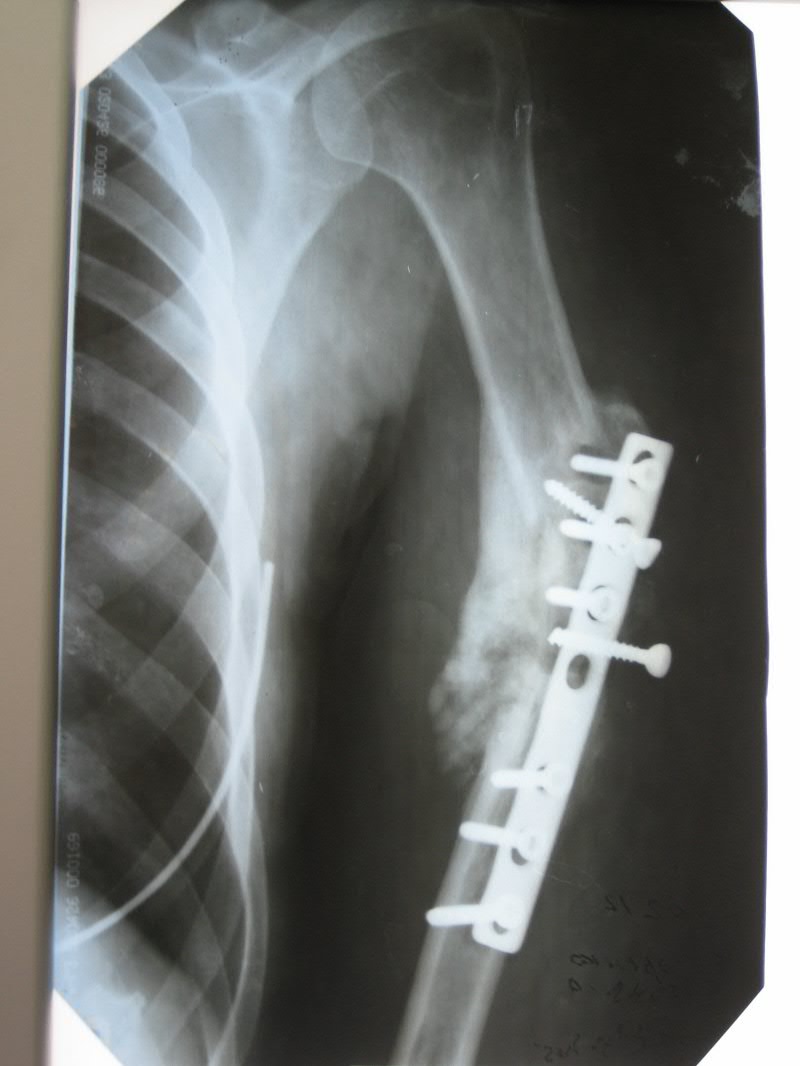

[Ortho] дефект-диастаз левой плечевой кости

п÷п╟я├п╦п╣п╫я┌п╨п╟ п╩п╣я┌ 40.

п■п╡п╟ пЁп╬п╢п╟ п╫п╟п╥п╟п╢ б═- п©п╣я─п╣п╩п╬п╪ п©п╩п╣я┤п╟.

п÷п╬я│п╩п╣п╢п╬п╡п╟я┌п╣п╩я▄п╫п╬ я│я┌п╟п╡п╦п╩п╦ я┌я─п╦ п©п╩п╟я│я┌п╦п╫я▀. п²п╟ п╡я│п╣ - п╬я┌я┌п╬я─п╤п╣п╫п╦п╣ п╪п╣я┌п╟п╩п╩п╟.

п║п╣п╧я┤п╟я│ - п╢п╣я└п╣п╨я┌-п╢п╦п╟я│я┌п╟п╥+я┐п╨п╬я─п╬я┤п╣п╫п╦п╣. п║я┐п╪п╪п╟я─п╫я▀п╧ п╢п╣я└п╣п╨я┌ п╬п╨п╬п╩п╬ 6 я│п╪. п■я▀я─п╨п╦ п╬я┌ п╡п╦п╫я┌п╬п╡. п≤п╫я└п╣п╨я├п╦п╦ п╫п╣я┌.